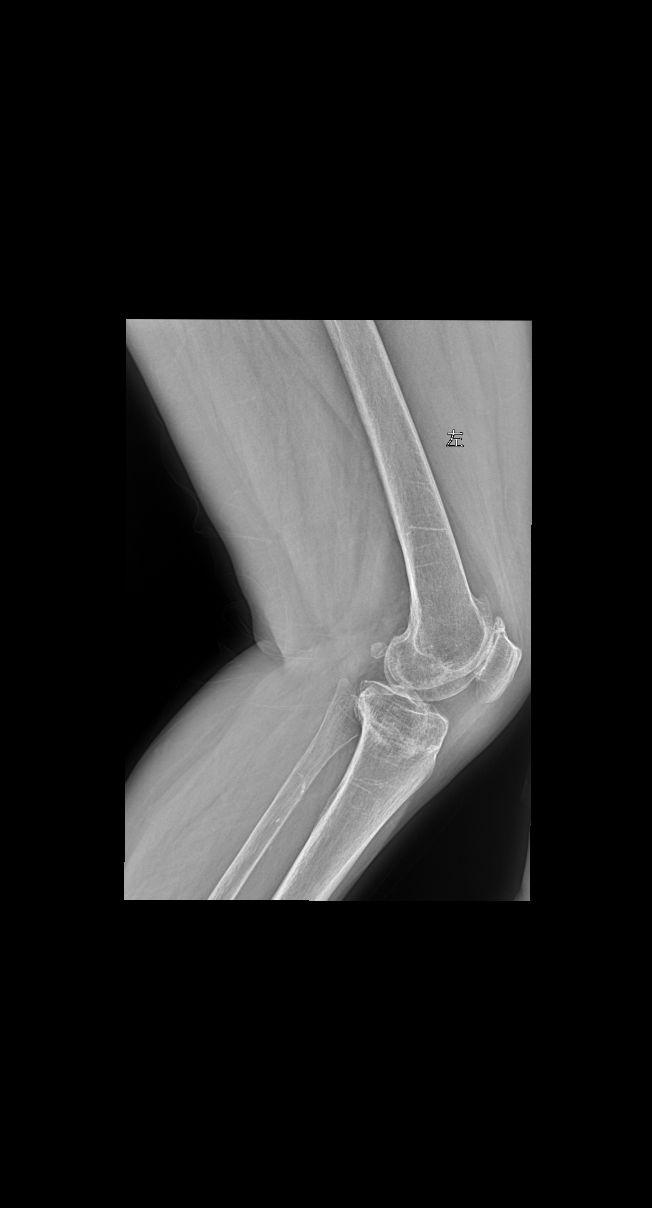

行走膝盖 脚底疼痛就诊 女69岁 考虑什么问题?